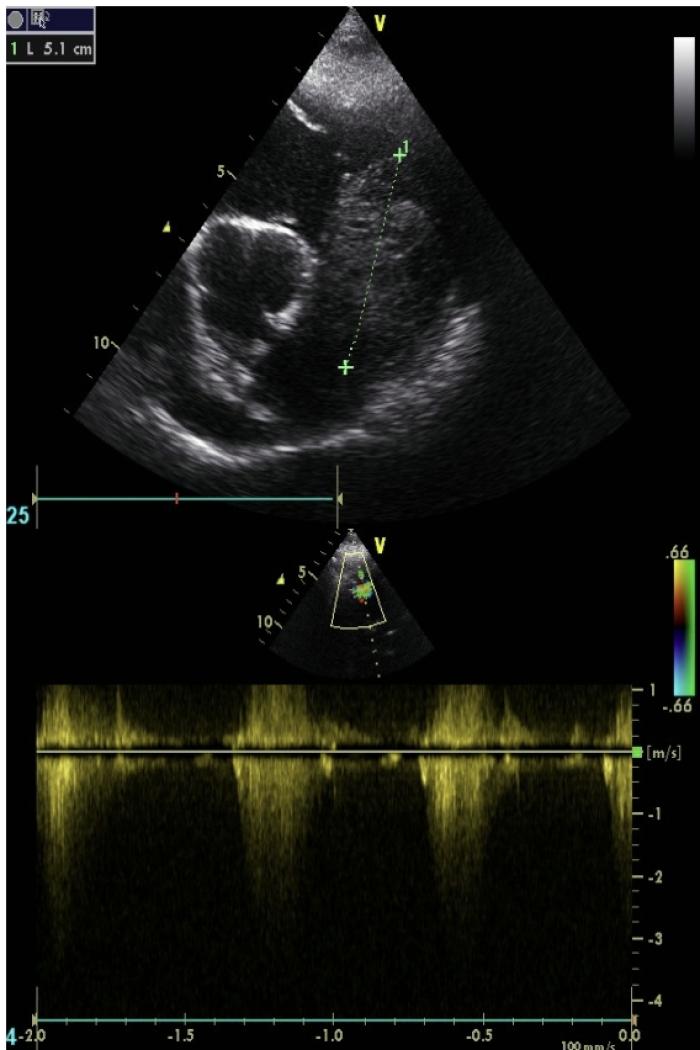

Durante la exploración física general el único hallazgo relevante es la presencia de un soplo mitral y una frecuencia cardiaca de 140 lpm. La ecocardiografíaconfirma la presencia de una masa en el ventrículo derecho (3.8 × 5 cm) (Figura 2 y 3), junto con insuficiencia mitral en estadio B2 e hipertensión pulmonar (consenso ACVIM). Se instaura terapia con clopidogrel (1.5mg/kg/día), para la prevención de tromboembolismo, y se sustituye el benaceprilo por pimobendan (0.5 mg/kg/12 h).

Se propone como diagnósticos diferenciales la presencia de un tumor cardíaco primario vs. metastásico, y se programa una tomografía computarizada (TC) toracoabdominal, para realizar estadio clínico completo, junto con una punción con aguja fina (PAF) de la masa intracardíaca, con el objetivo de obtener un diagnóstico presuntivo (Figura 4). Se añade cimicoxib (2 mg/kg/día) y toceranib fosfato (2.75 mg/kg, lunes-miércoles-viernes) hasta la obtención de los resultados. En la TC se confirma la presencia de neoplasia cardíaca primaria y la citología resulta compatible con un sarcoma, posiblemente un rabdomiosarcoma (RMS).